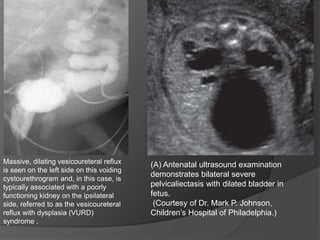

Massive, dilating vesicoureteral reflux

is seen on the left side on this voiding

cystourethrogram and, in this case, is

typically associated with a poorly

functioning kidney on the ipsilateral

side, referred to as the vesicoureteral

reflux with dysplasia (VURD)

syndrome .

(A) Antenatal ultrasound examination

demonstrates bilateral severe

pelvicaliectasis with dilated bladder in

fetus.

(Courtesy of Dr. Mark P. Johnson,

Children’s Hospital of Philadelphia.)

Massive, dilating vesicoureteralreflux is seen on the left side on this voiding cystourethrogram and, in this case, is typically associated with a poorly functioning kidney on the ipsilateral side, referred to as the vesicoureteral reflux with dysplasia (VURD) syndrome . (A) Antenatal ultrasound examination demonstrates bilateral severe pelvicaliectasis with dilated bladder in fetus. (Courtesy of Dr. Mark P. Johnson, Children’s Hospital of Philadelphia.)